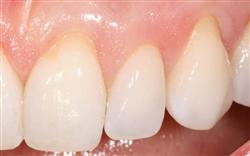

Cosmetic Soft Tissue Grafting

In addition to the functional problems previously mentioned, receding gums can look unsightly.

Longer looking teeth and exposed tooth roots give an "old" appearance to your smile. Some people cover their mouths when they smile for this very reason.

Cosmetic Soft Tissue Grafting can add a new youthful appearance to your smile. In your initial consultation with Dr. Hoidal, he will thoroughly explain what can be achieved in your particular case.